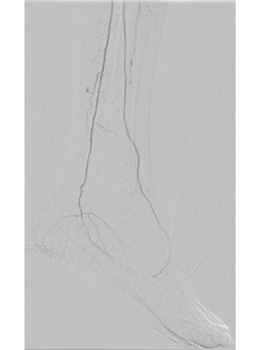

血管内治療(治療前)

血管内治療(カテーテル治療)

血管内治療(治療後)